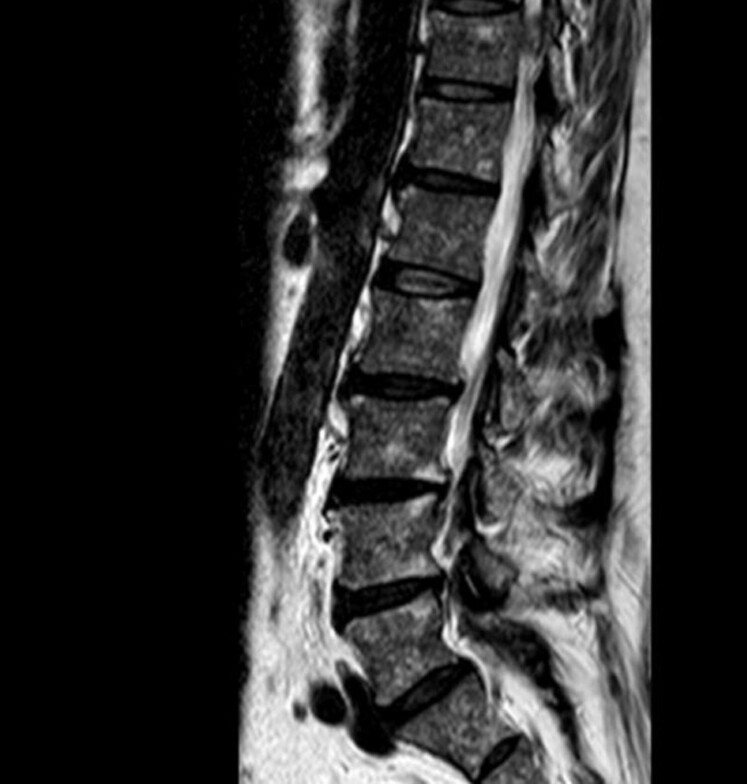

Clinical Features: The patient presented with low back and neck pain spanning 12 years and under the Veterans Affairs Medical Center was deemed 100% disabled.

Intervention & Outcomes: Lumbar Oswestry, Neck Disability, vitals, range of motion, orthopedic, and neurological exams were used to analyze physical examination findings both before and after spinal adjustment for vertebral subluxation. The patient was continually re-evaluated as care progressed over a 6-month period. The patient’s Lumbar Oswestry, Neck Disability Index, vitals, range of motion, orthopedic, and neurological findings all improved under care. Patient was able to resume ambulating unassisted and regained the ability to perform many activities of daily living.